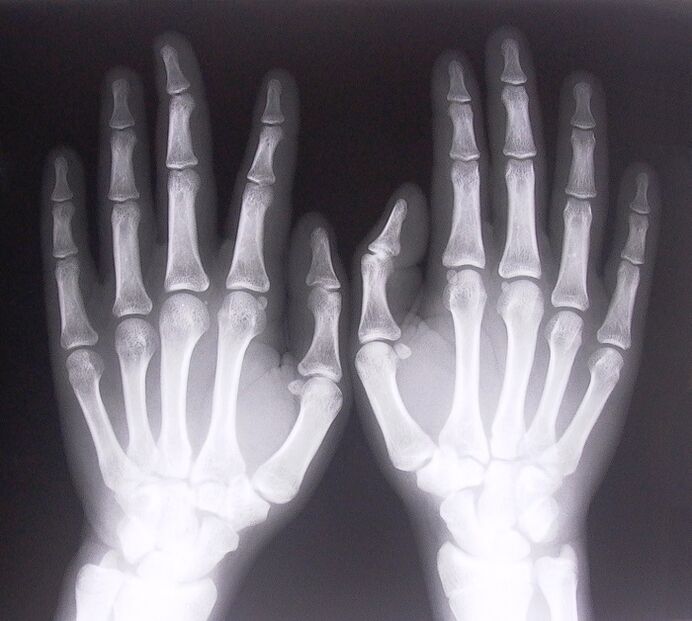

- Sténosing ligamentitis. Pikeun ngaidentipikasi panyabab panyakit, perlu ngajalanan x-ray. Gejala has: gerakan nyeri leungeun, looping tina lontar clenched. Ogé, salila extension, clicks biasana kadéngé.

- Candak x-ray.